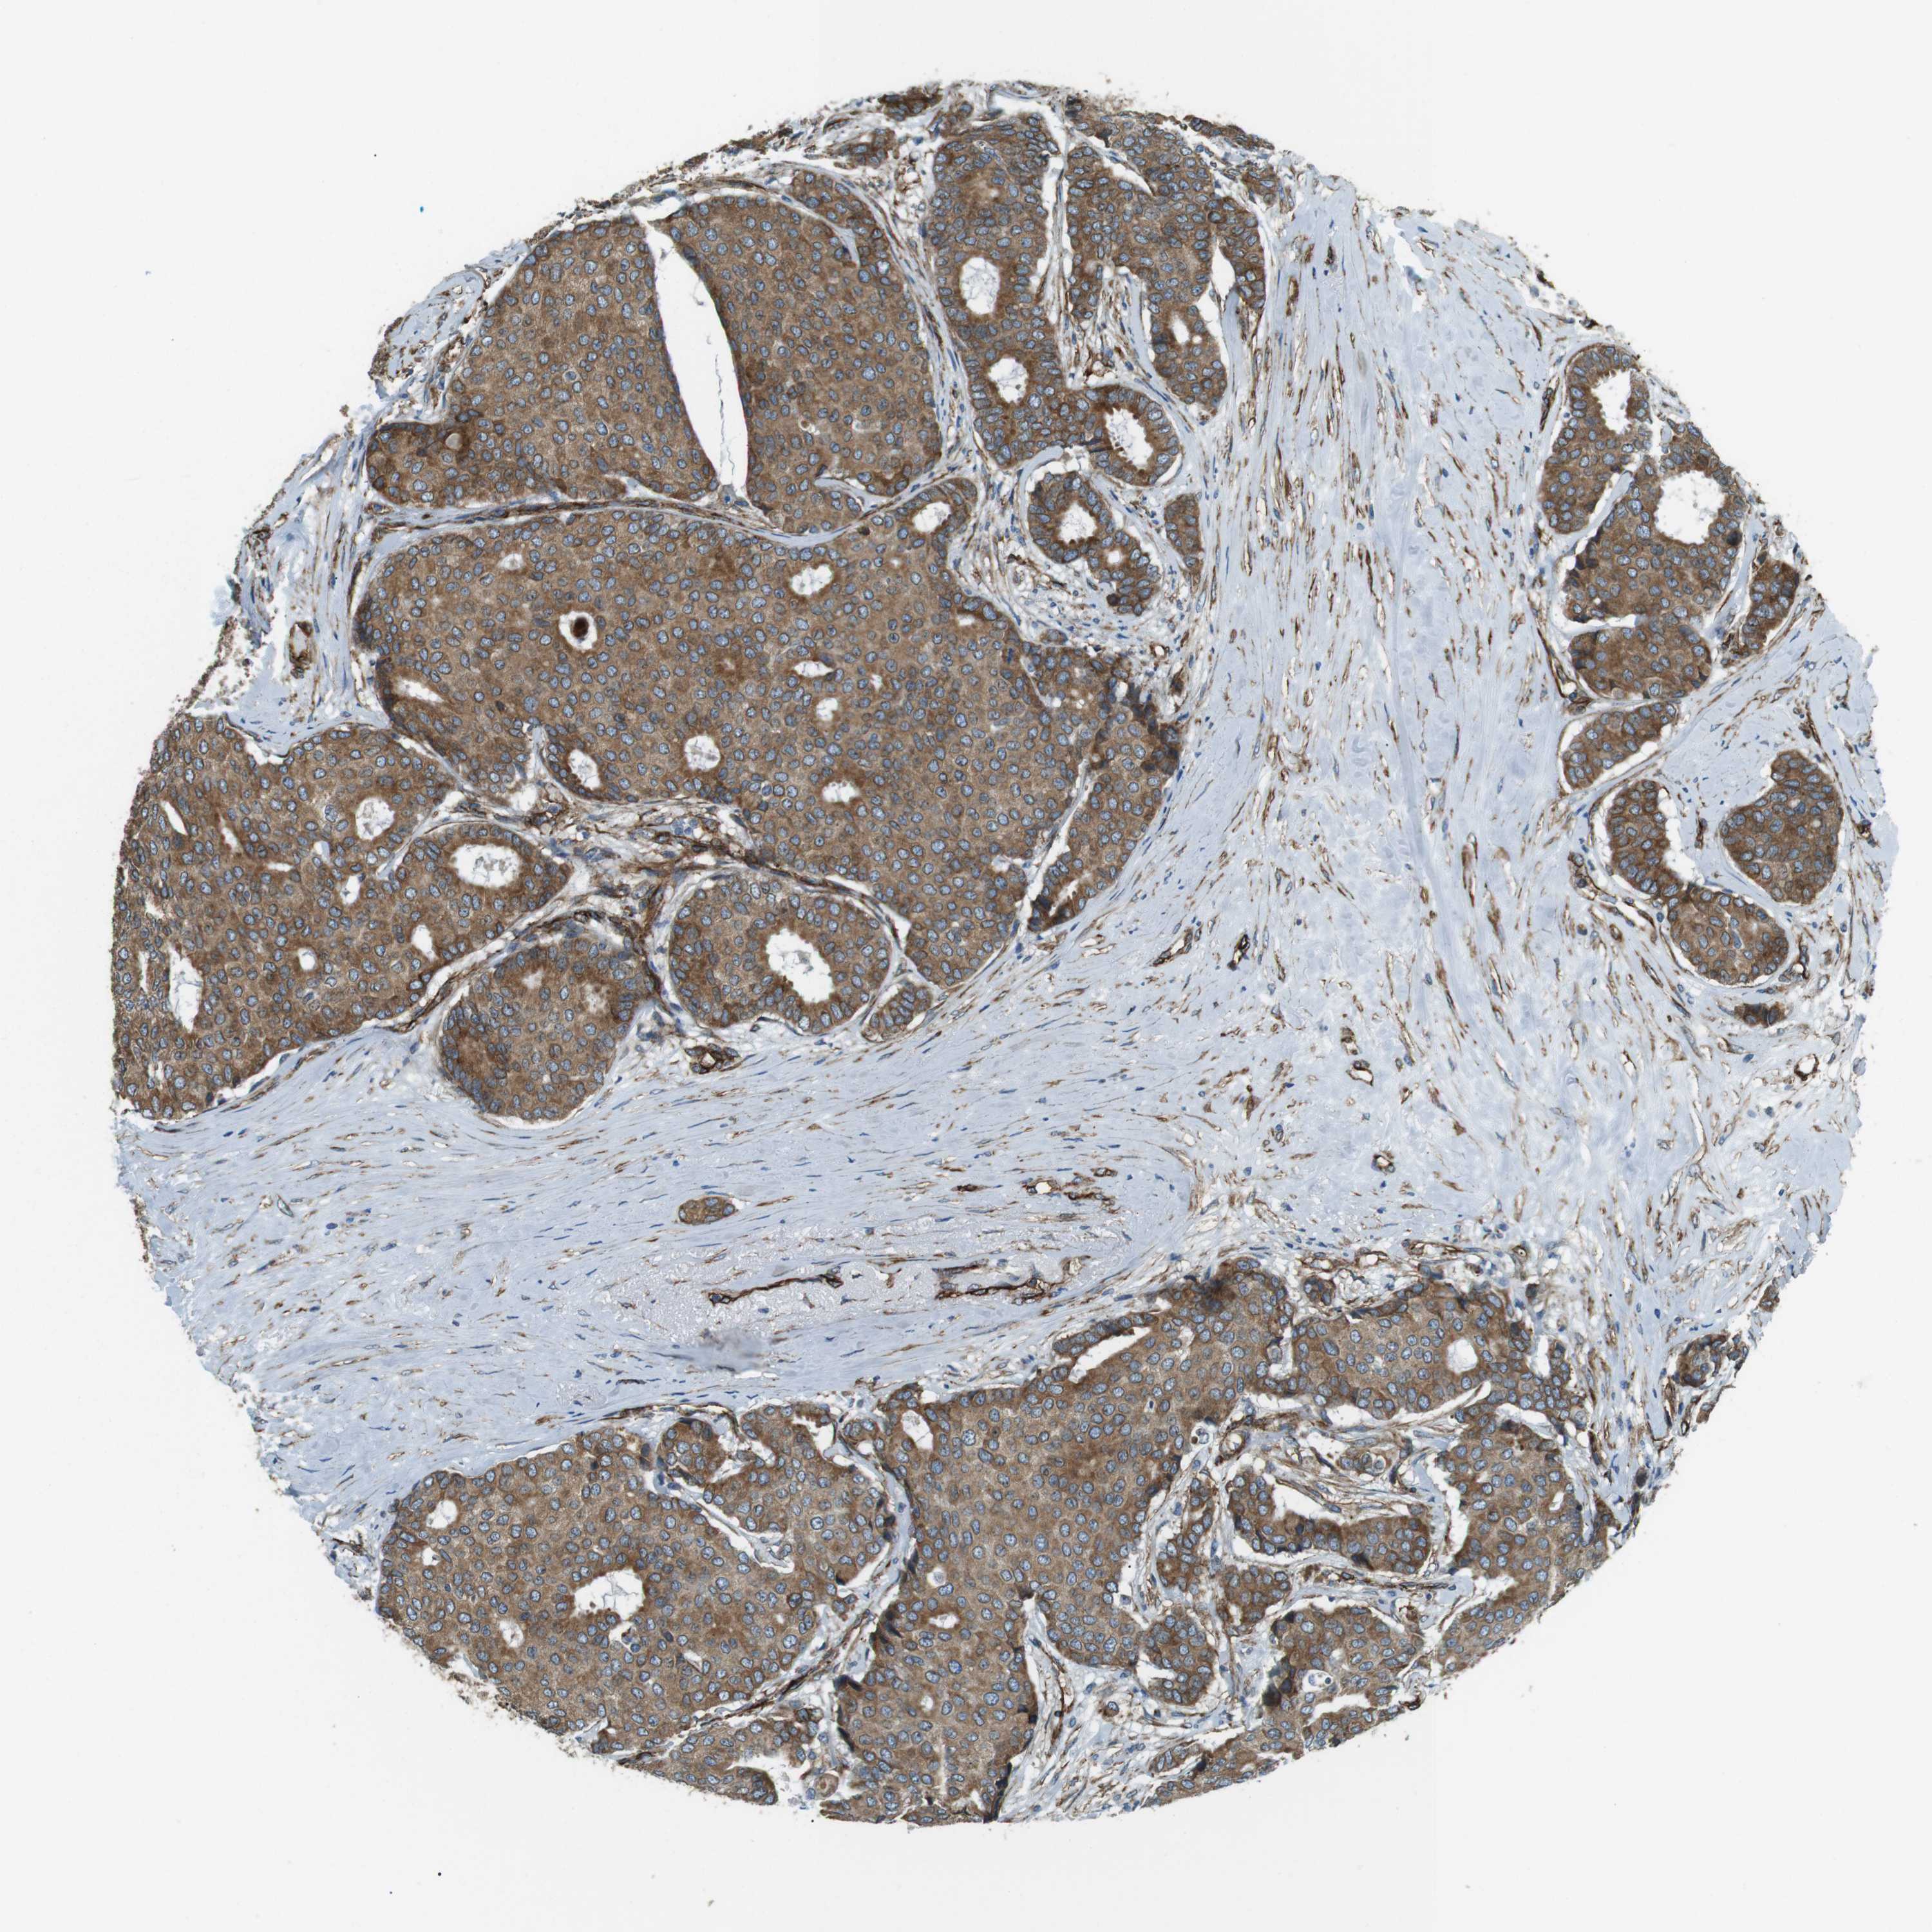

BRCA TCGA BRCA VALIDATION PROTEIN EXPRESSION

ANTIBODIES

AND

VALIDATION